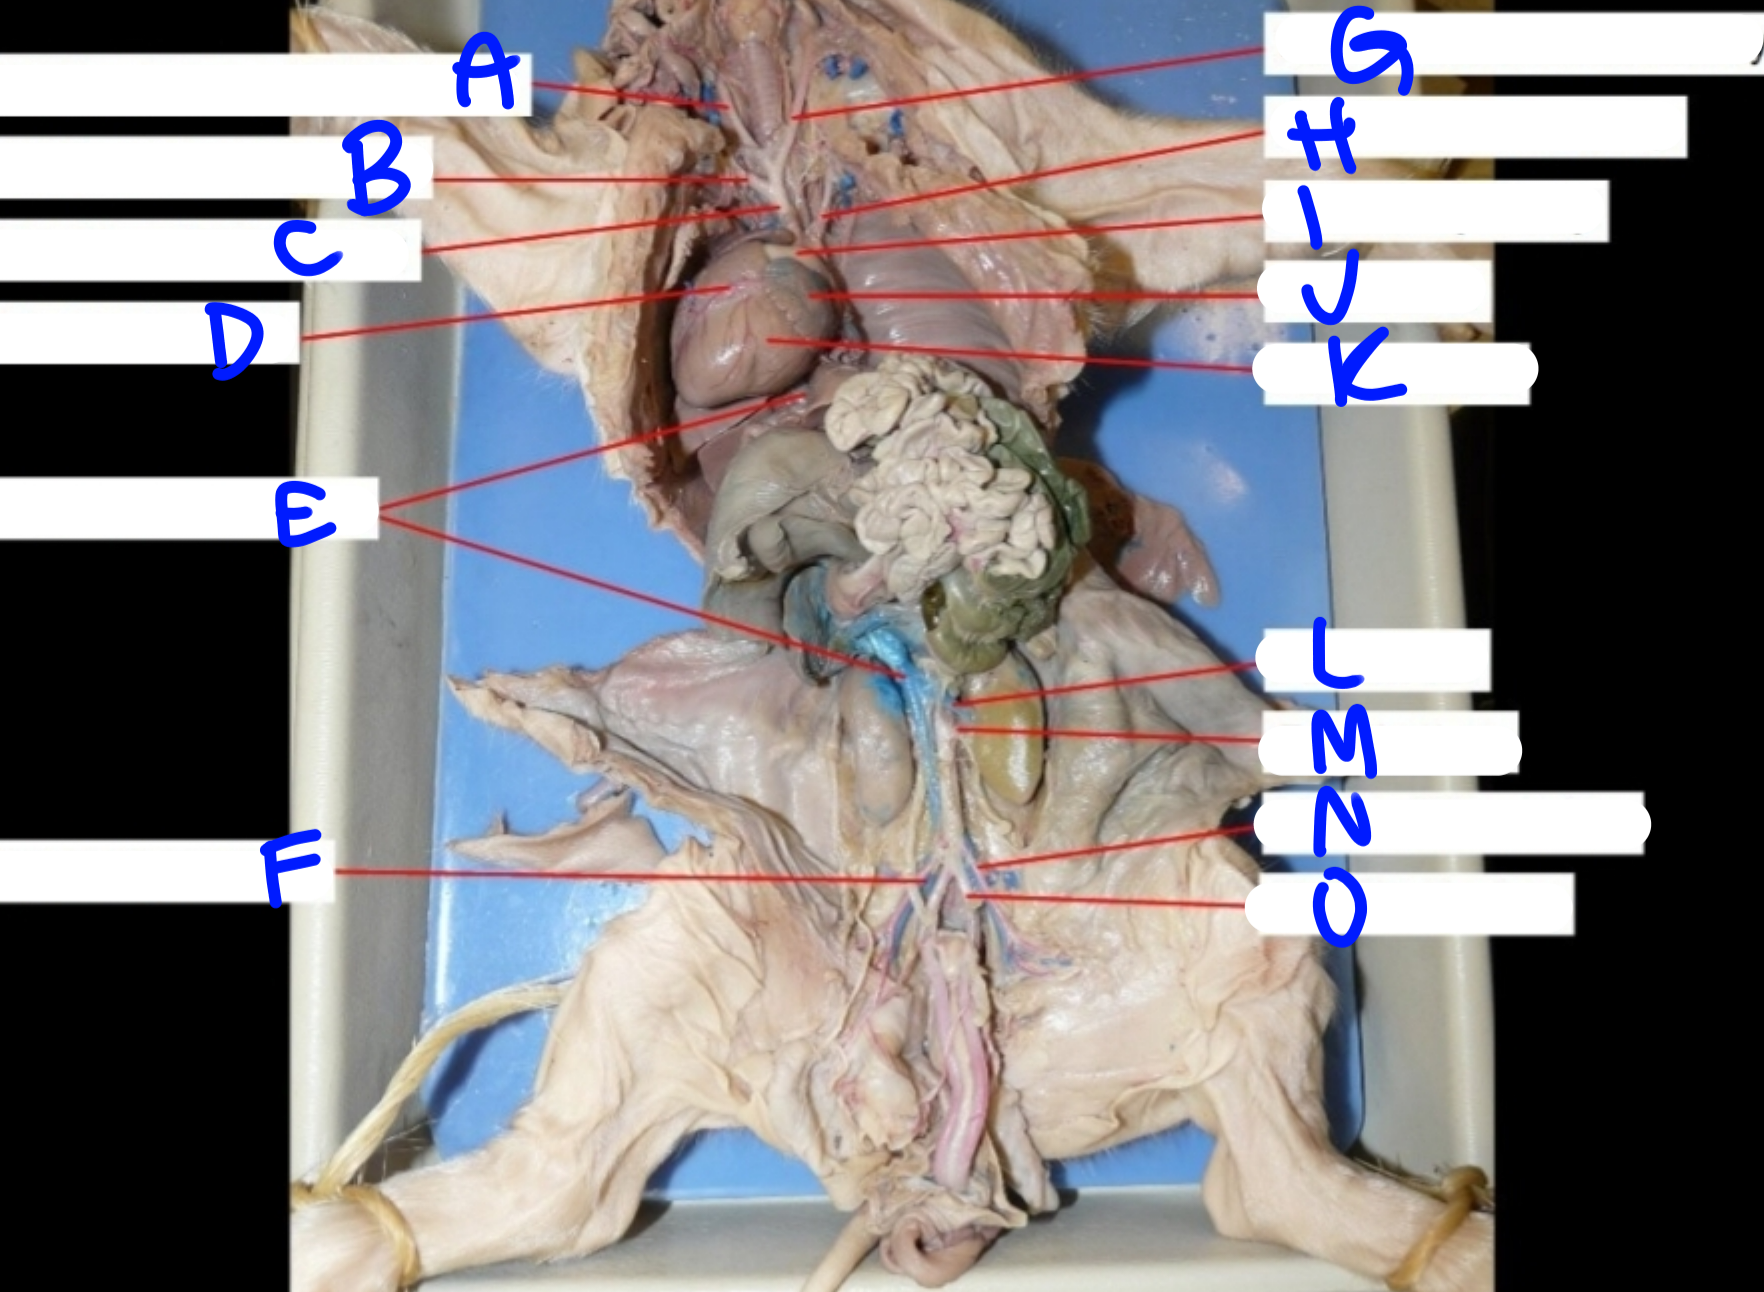

A

Right common carotid artery - delivers oxygenated blood to the head & neck

B

Right subclavian artery - delivers oxygenated blood to the upper body

C

Brachiocephalic artery - delivers oxygenated blood to the upper body

D

Coronary artery - delivers oxygenated blood to the heart

E

Posterior vena cava - carries deoxygenated blood from the lower body to the right side of the heart

G

Left common carotid artery - delivers oxygenated blood to the upper body

H

Left subclavian artery - carries oxygenated blood to the upper body

I

Pulmonary artery - delivers deoxygenated blood from the heart to the lungs

J

Left atrium - delivers oxygenated blood to the left ventricle

K

Left ventricle - delivers oxygenated blood to the systemic circuit

L

Renal vein - delivers blood from the kidney & ureter to the inferior vena cava

M

Renal artery - delivers blood from the kidney & ureter to the inferior vena cava

O

Umbilical artery - carries deoxygenated blood to the placenta